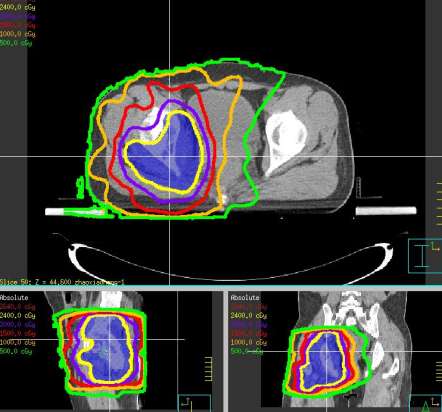

患者项xx,女,60岁,因咳嗽伴腰骶部疼痛2个月,加重1周入院。核磁:胸10椎体及附件转移继发椎管狭窄,脊髓受压;寰椎侧块膨大伴异常信号,不除外转移。临床诊断:左肺下叶腺癌(cT4N3M1,IV期),侵及降主动脉,双侧纵隔淋巴结转移,椎体转移,双肺炎,肝硬化-代偿期,高血压病3级(极高危险组),上消化道出血。患者骨痛剧烈,平车推入病房。2017年4月给予姑息减症放疗,靶区PTV1为胸10椎体及附件, 6MV-X线调强放疗,单次量8Gy,放疗组织剂量8Gy/1次/1天。放疗后疼痛缓解,现行动自如,靶向治疗中。